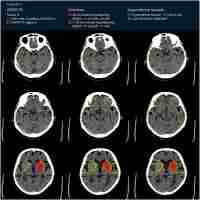

| Abstract | Objective: To investigate whether branch-site occlusion (BSO) sign could predict the etiology of acute intracranial large artery occlusion (ILVO) and the stentriever (SR) response. Methods: We systematically reviewed studies that evaluated the predictive role of BSO for the etiology of ILVO-AIS or EVT outcome between January 1, 2000, and August 31, 2022fromPubMed, Embase, and Web of Science. Results: The sensitivity and specificity of BSO sign predicting etiology of ILVO-AIS were 0.87 (95% CI 0.81-0.91) and 0.64 (95% CI 0.33–0.87), respectively(fig.3A). The sensitivity and specificity of BSO sign predicting stentriever response were 0.84 (95% CI 0.63-0.94) and 0.61 (95% CI 0.18-0.92), respectively. Conclusion: BSO sign could be a valid and precise imaging marker to predict embolism caused ILVO-AIS and recanalization success by SR without rescue therapy. |